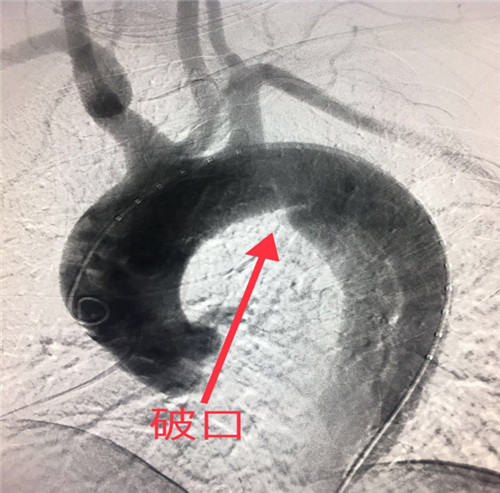

经过紧锣密鼓准备,于2018年6月3日为患者在局麻下成功施行了介入胸主动脉夹层覆膜支架腔内修复术。

胸主动脉夹层起病急、发展快、死亡率极高,若不及时有效治疗,48小时内死亡率70%左右,一周内的死亡率高达90%左右。该患者胸主动脉夹层破口距离左锁骨下动脉开口不足1厘米,为患者实施覆膜支架成功修复腔内破口、部分保留左锁骨下动脉避免了术后出现左上肢无脉症、脑缺血等严重并发症,该术式是目前主动脉夹层介入治疗的首选,较传统外科开胸手术创伤大、高风险、术后恢复慢,介入覆膜支架植入术具有微创、高效、安全等优势。